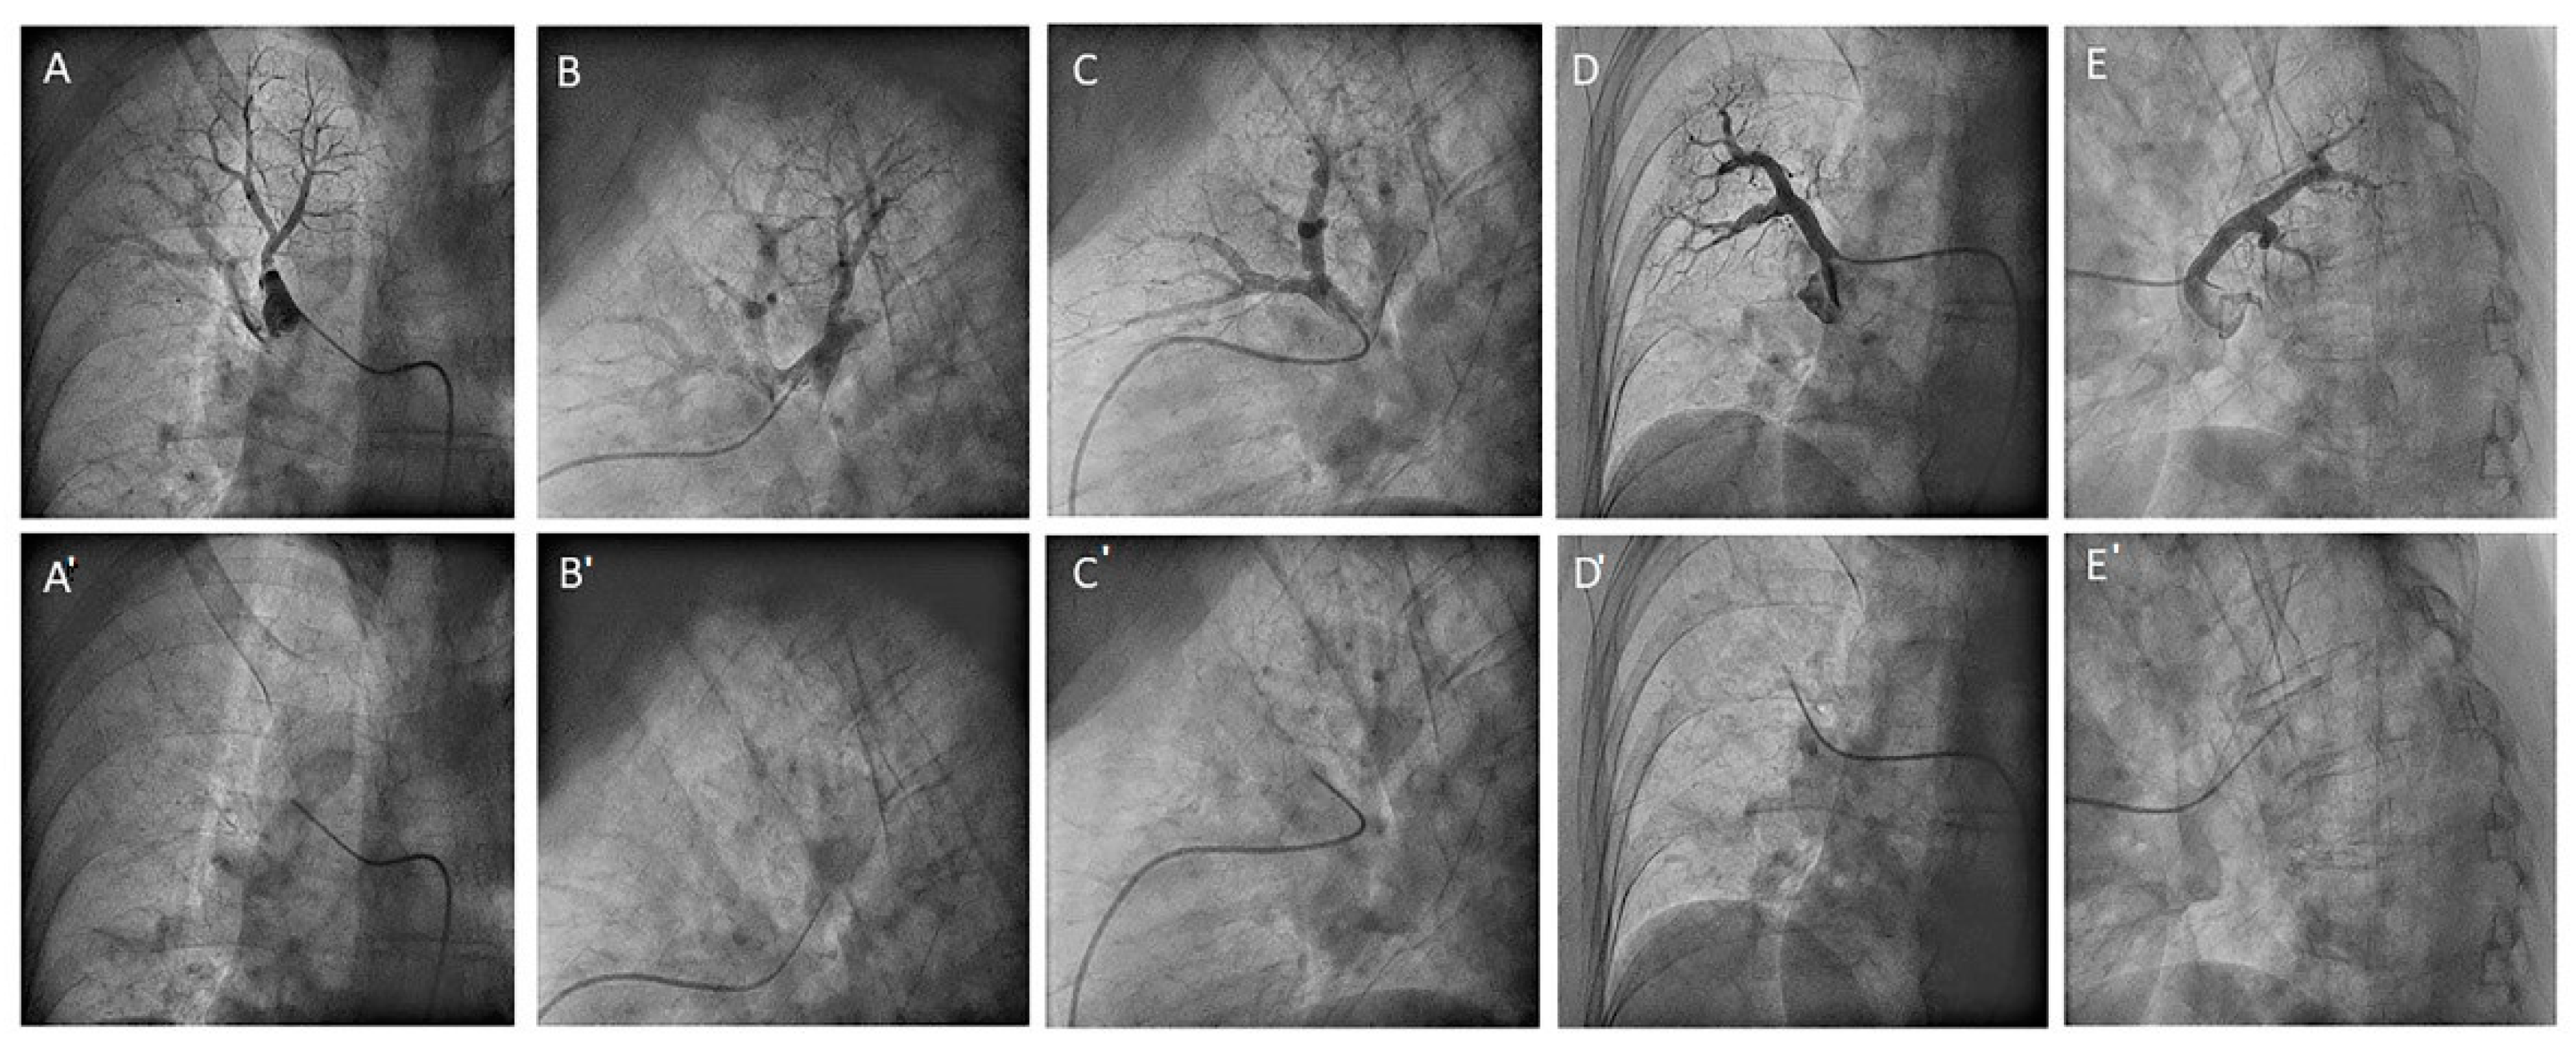

- Left upper lobe. The apico-posterior trunk (A1/2) is easily cannulated in the AP view. We should rotate the MP-A2 catheter counterclockwise in the proximal segment of the LPA to make the tip face upwards (Figure 23). The apical and posterior segmental arteries (A1 and A2) are well visualized by filming in the AP and lateral views. The anterior segmental artery (A3) is engaged more easily with the Judkins left catheter (JL) 3.5 or 4. Position the JL below the aortic arc in the AP view with the distal tip facing the left lateral chest wall. Rotate the catheter counterclockwise and withdraw it slightly. The distal tip of the catheter will climb 2–3 cm, engaging the anterior segmental branch (A3) (Figure 24). Film this branch in the cranial RAO and lateral views.

- Lingula. The lingula artery is easily cannulated in the AP view with the JL 3.5/4 catheter (depending on the PA dilatation). The maneuver and position in the AP view is the same as described for the anterior segmental artery of the left upper lobe (A3), though somewhat lower (Figure 25). Amplatz left 1 or 2 is also a good choice for catheterization of the lingula branches. In addition, this catheter gives extra support when performing BPA of these branches. The two lingula segmental arteries are well displayed in the lateral and in the cranial RAO/cranial AP views.

- Left lower lobe. The two trunks of the basal pyramid and the superior segmental artery (A6) are easily cannulated with the MP-A2 in the lateral projection (Figure 26). The anterolateral trunk (A8/9) sometimes requires the Judkins right (JR) 4 or the JL 3.5/4. We should sequentially film both trunks and the superior segmental artery (A6) in the lateral and AP view.